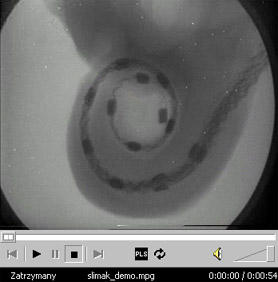

![Kliknij aby obejrzeć prezentację o umiejscowieniu elektrod wewnątrz ślimaka [9,14MB]](psycho/grafika/slimak_demo.jpg)

Elektrody umieszcza się wewnątrz ślimaka na błonie podstawowej (jest ich najczęściej kilkanaście). Każda z nich pobudza inną część ślimaka (błony podstawowej) odpowiedzialną za przenoszenie informacji o innym paśmie częstotliwości dźwięku (w procesorze mowy pasmo analizowanego dźwięku dzielone jest na taką ilość podpasm, jaka jest ilość elektrod) . Impulsy podawane są tylko na jedną elektrodę w danej chwili (w przypadku pobudzania paru elektrod jednocześnie dochodziło do zakłóceń w pracy).